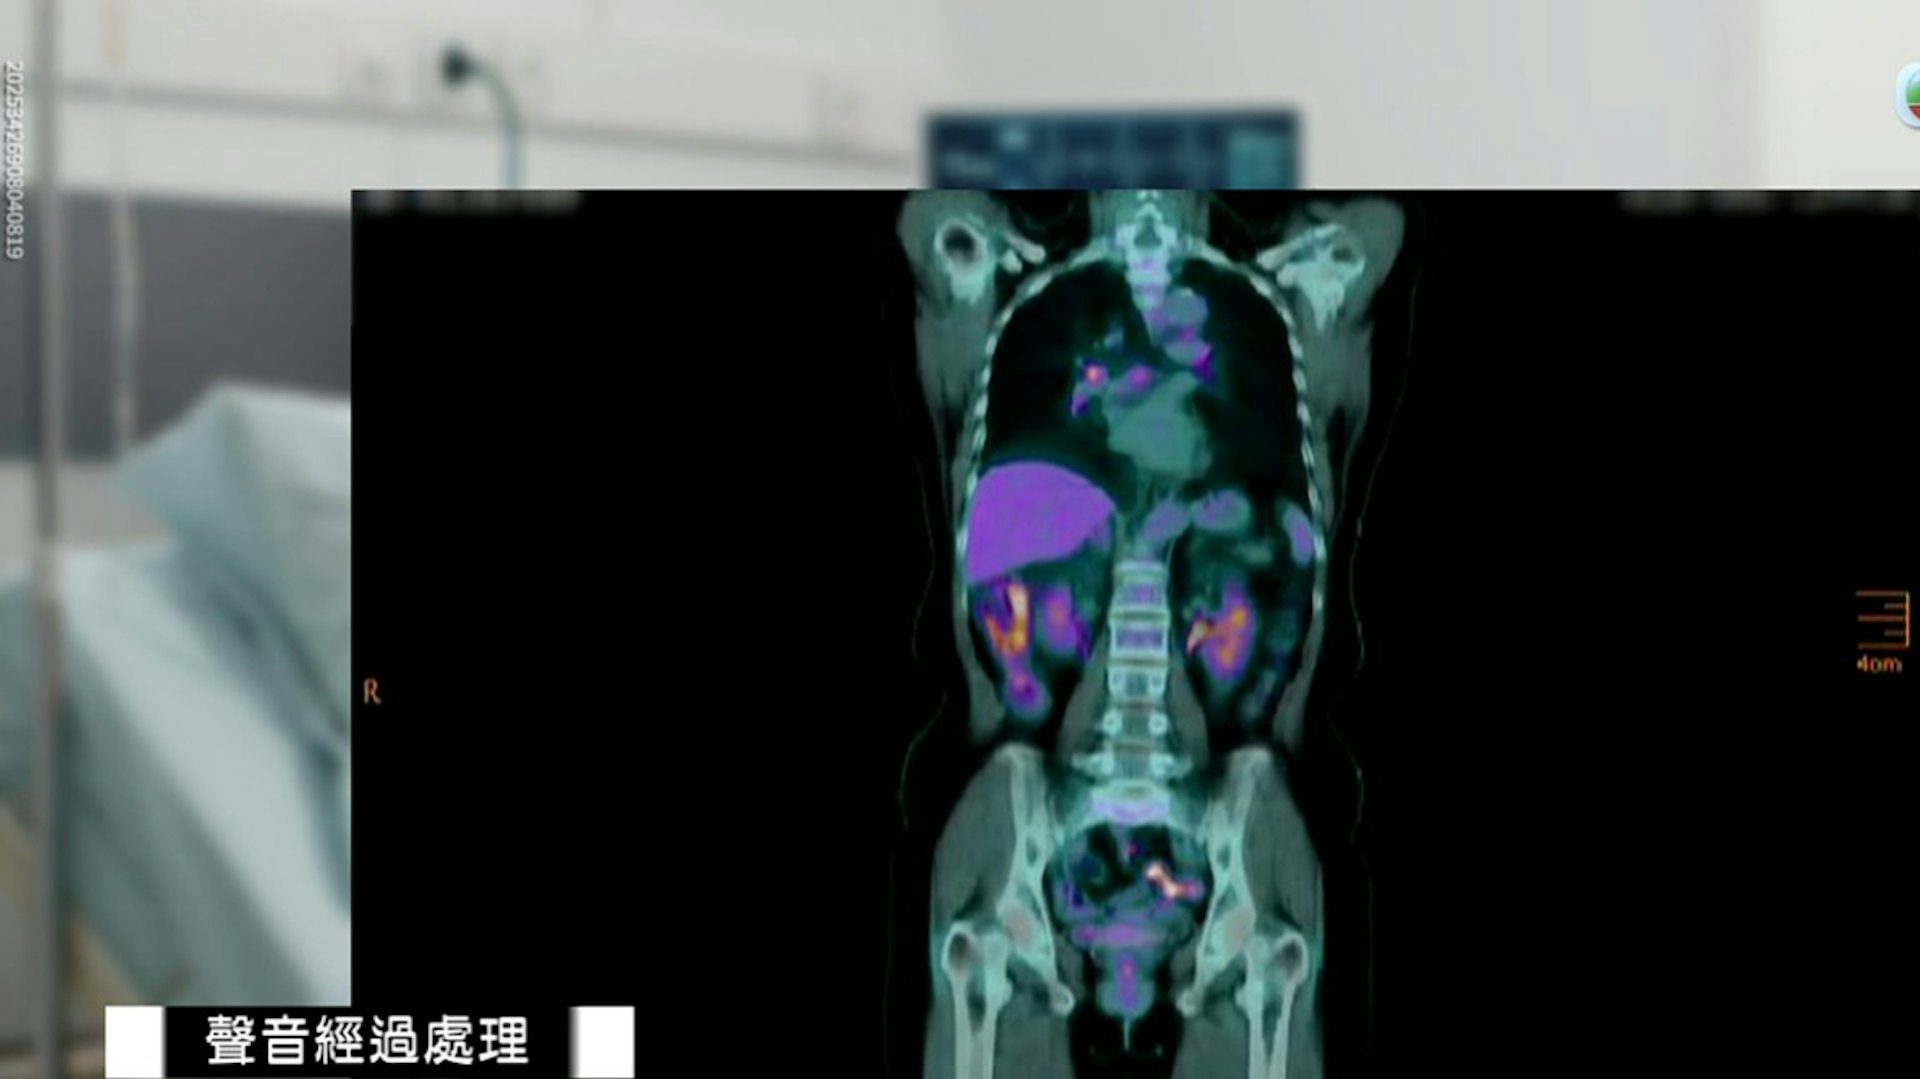

3 F c# v& @- M* [TVBNOW 含有熱門話題,最新最快電視,軟體,遊戲,電影,動漫及日常生活及興趣交流等資訊。據8月19日至21日的《東張西望》,張先生母親去年確診胰臟癌,經歷多次化療後原定接受電療。惟今年2月突然吐血,緊急被送往將軍澳的一間醫院。醫生建議進行內視鏡超聲波穿刺手術,並強調成功率達八至九成。但手術期間,張母心臟一度停頓20分鐘,搶救後情況危殆,並出現嚴重內出血。最終她在手術翌日凌晨離世。: N2 B3 p* S3 _& E0 p5 f: W# a7 y

經檢查後,張媽媽吐血的原因是腫瘤壓住12指腸,導致潰瘍及流血。(《東張西望》節目截圖)TVBNOW 含有熱門話題,最新最快電視,軟體,遊戲,電影,動漫及日常生活及興趣交流等資訊。5 p" G& K* P$ O% \. Q2 X